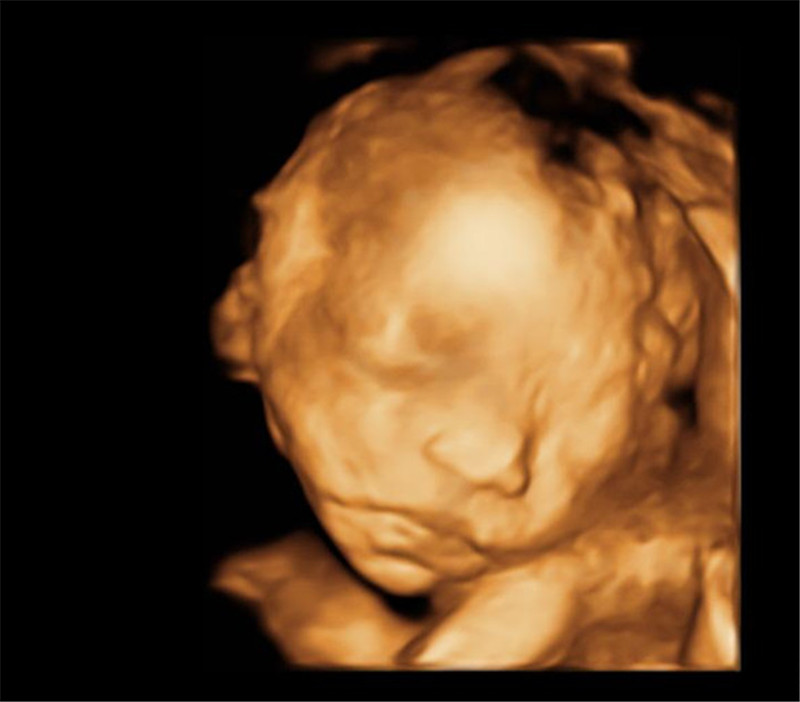

2. Real-time dynamic moving images: It can display real-time dynamic moving images of your unborn baby, or real-time moving images of other internal organs.

4. Multi-dimensional and multi-angle observation: Four-dimensional B-ultrasound can observe the growth and development of the fetus in the uterus from multiple directions and angles, and provide accurate scientific basis for early diagnosis of fetal congenital surface deformities and congenital heart disease.

5. Physical examination of the fetus: In the past, B-ultrasound equipment can only check the physiological indicators of the fetus, and four-dimensional B-ultrasound can also inspect the fetal body surface, such as cleft lip, spina bifida, brain, kidney, heart, and bone dysplasia .